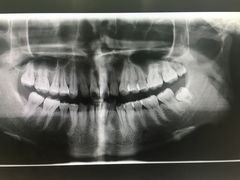

• 固瑞齿科(国贸门诊店)

• -固瑞齿科(国贸门诊店)

点小评8685146021 | 18-12-31

报错